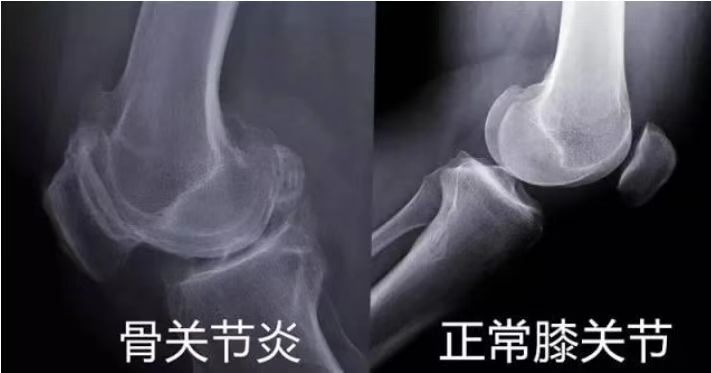

发表时间:2023-06-02 15:51 膝关节骨性关节炎(OA)又称退行性骨关节病,属于关节提前老化,特别是关节软骨老化,是一种由于关节软骨退行性变,引起的关节软骨完整性破坏及关节边缘软骨下骨板病变,继而导致关节症状和体征的一组慢性退行性关节疾病,被认为是一种慢性疾病会使患者关节疼痛、僵直畸形、功能障碍,多见于中老年人。 骨性关节炎是最常见的关节炎形式。最早体现在手的小关节,它是一种影响关节所有组织的疾病,包括软骨,骨骼,韧带和肌肉。但最常见的是影响膝关节、髋关节、脊柱、手等部位,其中膝关节炎占41%。好发年龄通常在 50 岁之后,如果有关节损伤,发生会更早开始。它会干扰患者对生活的享受,尤其是喜欢户外运动的。膝关节是最常见的下肢关节。患有骨性关节炎的人在进行常规活动(例如步行和上下楼梯)时经常会出现膝盖疼痛。 ![]() 根据骨关节炎累计部位,分为内侧侧室、外侧间室、髌股间室骨关节炎。在膝关节骨性关节炎中,导致骨骼(股骨和胫骨)、关节和软组织发生病理改变,从而导致疼痛,关节僵硬,关节活动度减少,步态异常和肢体不等长,继而累及髋和踝关节,甚至腰椎疾病。下肢负重轴线(内翻畸形、外翻畸形、旋转畸形、短缩畸形、侧方移位畸形和复合畸形)异常会出现什么情况呢? 下图显示当对线异常的时候,内侧负荷增加,软骨磨损,导致膝关节疼痛。 ![]() OA被认为是一种慢性疾病,老年膝关节疼痛在临床上非常常见,传统治疗手段有非手术和手术治疗,后者典型代表是膝关节表面置换手术,解除病人疼痛,恢复行走功能,但术后满意仅有82%,术后不能获得较高的运动能力和关节屈伸活动能力。 ![]() 临床表现: